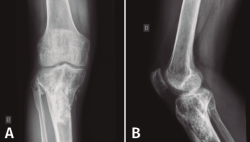

Figura 5. Radiografías de frente y de perfil del extremo proximal de la tibia donde se objetiva la cavidad en la tibia con presencia de material granulado en su interior.

En el estudio radiológico (Figura 5) se objetiva imagen cavitaria en el extremo proximal de la tibia con presencia de material granulado del injerto realizado.

Figura 7. Radiografías de frente y de perfil del extremo proximal de la tibia tras el desbridamiento de la cavidad y el relleno con bolas de cemento con antibiótico.

Con el diagnóstico de osteítis crónica de la tibia se realiza desbridamiento óseo de la cavidad y amplia resección ósea de cortical tibial medial, y relleno de la cavidad con bolas de cemento con antibiótico (Figura 7), con posterior tratamiento antibiótico.

Figura 8. Radiografías del extremo proximal de la tibia donde se objetiva la correcta incorporación del injerto aportado.

Al cabo de 4 meses y tras la resolución del proceso séptico, se procede al relleno de la cavidad con injerto autólogo de cresta iliaca, cuya evolución fue hacia la incorporación de este (Figura 8).